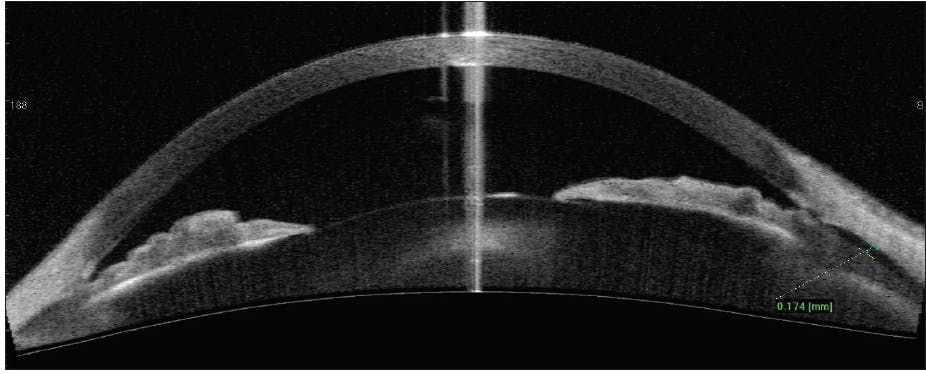

Anterior segment OCT (AS-OCT) was particularly helpful in showing shallowing of the anterior chamber in the right eye, with a closed angle and a reduction in anterior chamber volume from 21.64 mm2 to 14.94 mm2 (Figure 1). Given the patient’s progressive myopia, anterior chamber shallowing, and angle closure despite normal IOP, a diagnosis of spontaneous malignant glaucoma was made.

Figure 1. AS-OCT imaging of the right eye (A) and left eye (B) using the Cirrus HD-OCT 5000/500 (Carl Zeiss Meditec) and an anterior chamber lens.

Courtesy of Georges M. Durr, MD, FRCSC